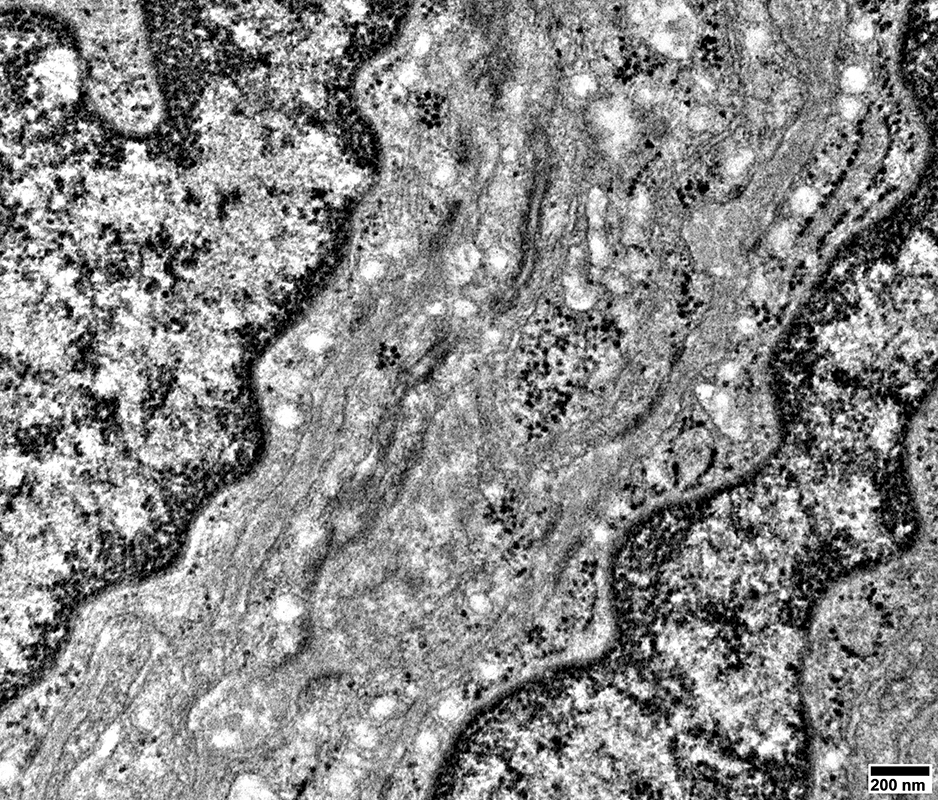

Perineurioma: Ultrastructure

From: R Schmidt

Perineurioma

Perineurial tumor cells in endoneurium (Black arrow)

Long processes containing small round vesicles

Unmyelinated axons

Surrounded by thin Schwann cell processes (Red arrow)

Processes contain

MBP but not

NCAM

Large collagen pockets are present (White arrow)